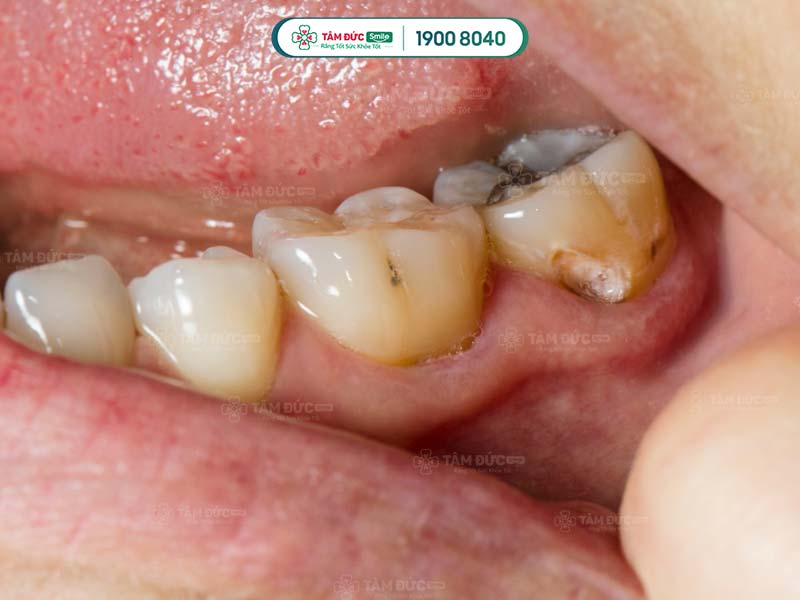

1.1. Bề mặt răng có các đốm nâu đen

Đây là dấu hiệu điển hình nhất khi răng khôn bị sâu. Các đốm nâu đen này xuất hiện do vi khuẩn sâu răng tấn công và ăn mòn men răng, gây sâu răng.

dấu hiệu sâu răng khôn